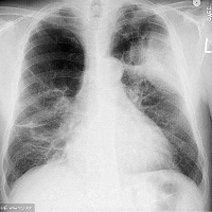

白肺的意思是指胸片、CT上发现正常肺组织透X线是黑色,只有心脏和大血管是白色,但是由于各种疾病、各种致病因素,导致两肺野呈大片的密度增高,出现白色的阴影,就...47600人收听

白肺一般是指重症肺炎在X光检查下的表现,肺部呈现一大片的白色状态而闻名。形成白肺一般都预示着肺部被炎症所广泛浸润,引起白肺的病因往往非常复杂,并且来势凶...28117人收听

白肺是指患者在X光胸片检查或者肺部CT检查中,肺部间质组织呈现大片状白色状病变的表现。白肺的症状表现多发生于重症肺炎,因为肺部间质组织持续性受到病毒、细...60057人收听

白肺(White lung)是一种临床综合症,其特征是重度肺炎患者的肺部积累了大量渗出物,影响多个肺叶,使肺部影像学检查呈现出大范围的白色区域。病因多为新型冠状病毒感染、细菌性肺炎、中东呼吸...

[最佳答案] 白肺是放射学名词,所谓白肺是指胸片或者CT上弥漫的高密度影,使得片子看不到肺纹理。导致白肺发生的原因很多,常见的大叶性肺炎、肺水肿,或者是病毒性肺炎比如SARS,以及流感、病毒引起的肺炎都会导致白肺。 至于能不能治愈要根据疾病的不同来决定, 白肺是放射学名词,所谓白肺是指胸片或者CT上弥漫的高密度影,使得片子看不到肺...